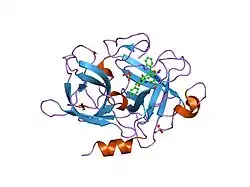

Urokinase is a 411-residue protein, consisting of three domains: the serine protease domain (consisting of residues 159–411), the kringle domain (consisting of residues 50-131), and the EGF-like domain (consisting of residues 1-49). The kringle domain and the serine protease domain are connected by an interdomain linker or connecting peptide (consisting of residues 132–158). Urokinase is synthesized as a zymogen form (prourokinase or single-chain urokinase), and is activated by proteolytic cleavage between Lys158 and Ile159. The two resulting chains are kept together by a disulfide bond between Cys148 and Cys279.[9]